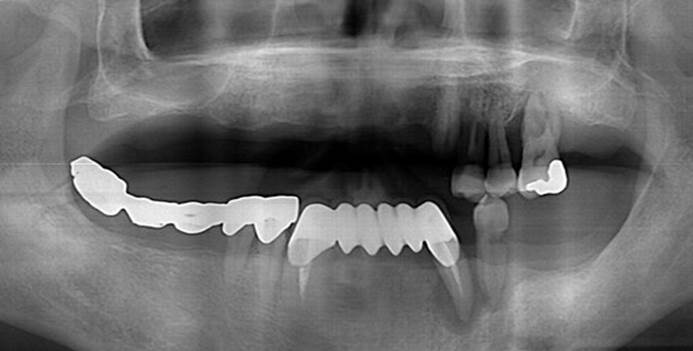

Clinical case: Extraction of all teeth in upper maxilla,

immediate implant placement, & provisionalization

- Courtesy of Dr. Iulian Filipov, Romania -

Keywords

AnyRidge, immediate placement, immediate provisionalization, maxillary fully edentulous case, initial stability, edentulous, Dr. Iulian Filipov, R2GATE, MEGA ISQ

Products:

AnyRidge implant system, Mega ISQ, R2GATE